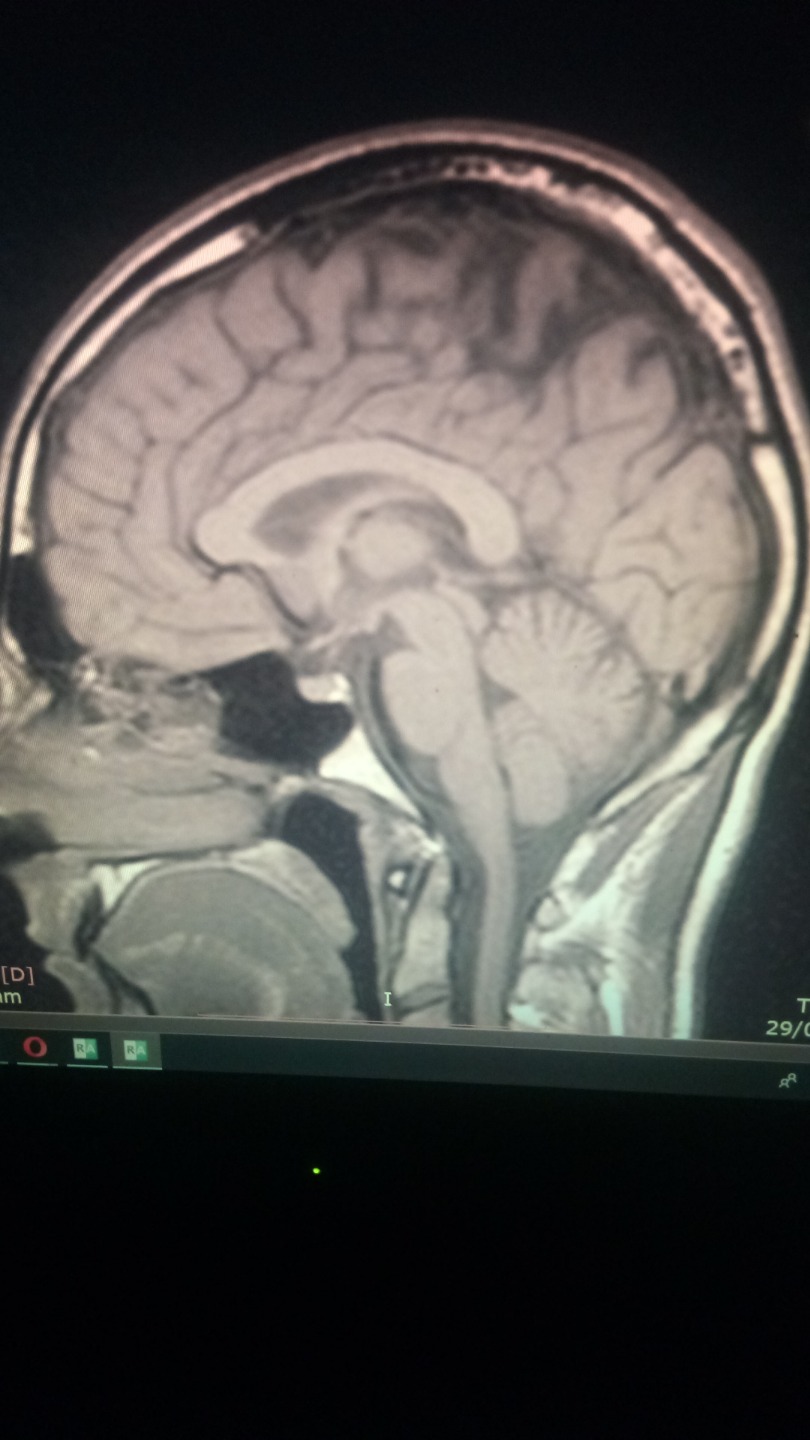

PD : Will atach a photo of my brain, if anyone knows how to read mri scans and know what is going on on my brain is real apreciated. I just think is a infection that somehow is cicatrized thanks to mms.

Neurologist says I have nothin, I dont believe him.

the infection ( look at the pics of my brain mri, i had not headaches, nor nothing, but my brain was having an infections, i noticed something was wrong because i had insomnia for 3 months , like real hardcore insmonia, visual snow, poor memory and concentration, joint paints, dificulti breathing (babesia like simptom) coughfin, and stuff like that. But it wasnt like a normal type of cold. It was weird. I got headeaches when I started to take mms, specially big doses of 15 drops. less than that and standart protocol 1000 was not effective.